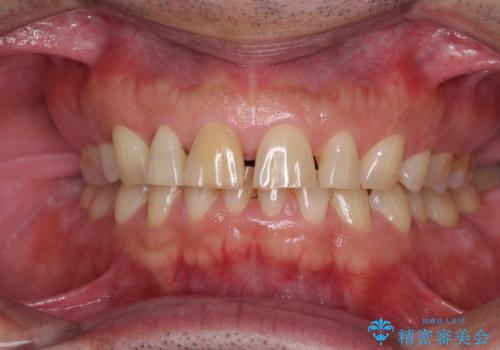

- 前歯の目立つ隙間を気にして来院された患者様です。

高校生の頃に矯正治療を行ったものの、強い咬合力により上顎が拡大され、正中に隙間ができてしまいました。

通常では歯の周囲全体を削った上でクラウンを装着することが多いのですが、咬合力が非常に強く、クラウンではセラミックが欠けてしまう可能性が考えられたため、咬合を変えることとのないラミネートベニアにて治療を行うこととしました。